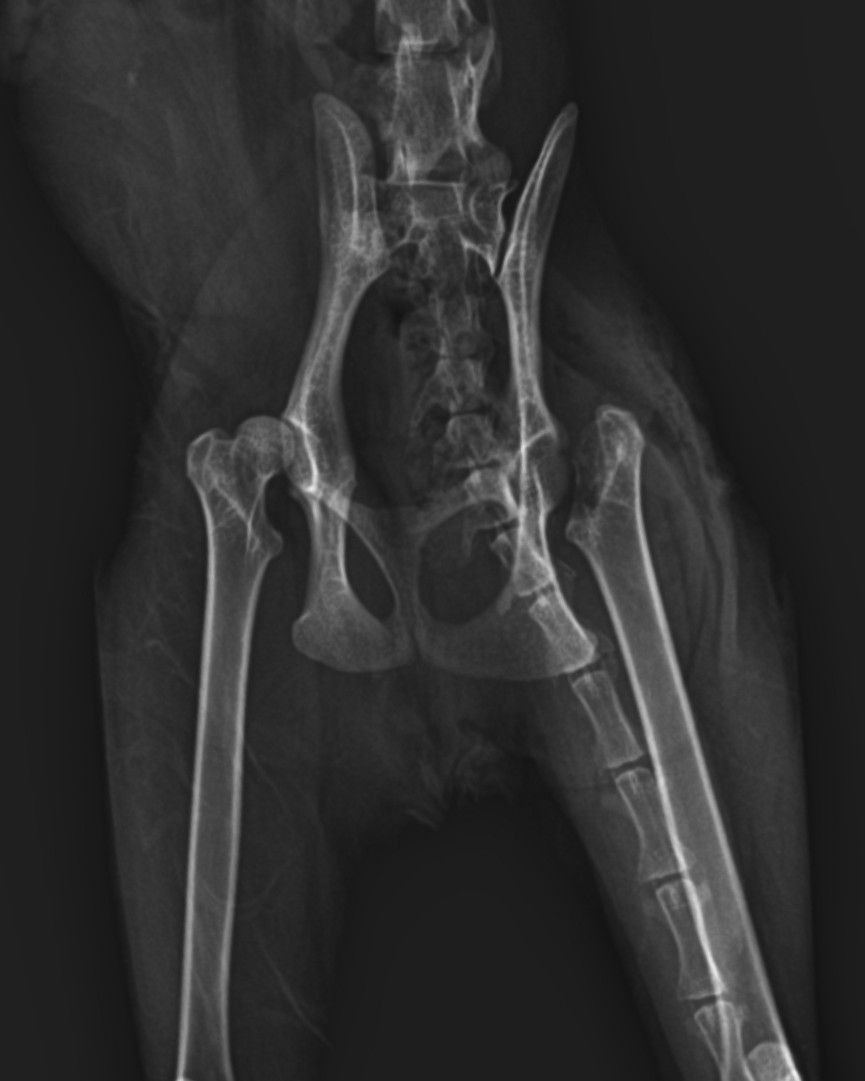

Femoral Head Ostectomy

Femoral Head and Neck Ostectomy (FHO) is a salvage surgical procedure performed to eliminate pain and restore functional limb use in animals suffering from severe hip joint

disease

The surgery involves removing the femoral head and neck, thereby eliminating bone-to-bone contact and allowing a fibrous pseudoarthrosis (“false joint”) to form

A 1.5-year-old male Scottish Shorthair cat was presented to the clinic with a history of progressive hindlimb lameness and difficulty jumping.

The owner reported that since early age, the cat had shown stiff movement, reluctance to climb, and occasional vocalization when handled.

No history of trauma was noted. The condition gradually worsened, affecting both hindlimbs mor severe in the right hind limb

• Bilateral hindlimb lameness with a “bunny-hopping” gait pattern

• Pain and crepitus upon hip manipulation

• Positive Ortolani sign confirming hip joint laxity

• Normal neurological function

Bilateral FHO was recommended starting with the right most affected limb and the other to be scheduled after 2 months